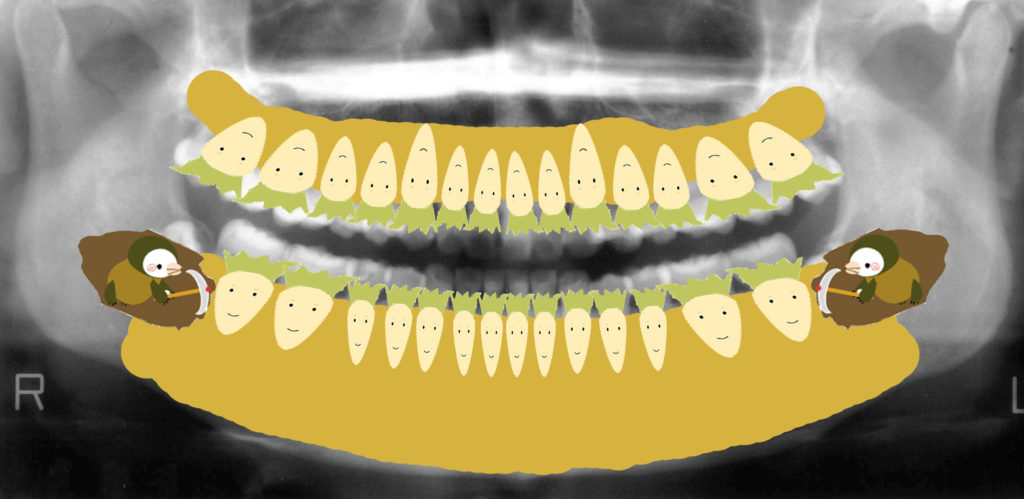

私は患者さんに説明するとき、よく「畑に大根が植わっているイメージ」とお伝えしています。

黄色い部分が畑(土=骨)、白い大根が歯です。

親知らずは隣の歯を圧迫し、どんどん食いつぶしていきます。

放置すると隣の歯もダメージを受けるのです。

畑(骨)に大根(歯)が植わっているイメージ

このレントゲン図をイラストにしてみました。

私はよく患者さんにお話しする時「畑に大根が植わっていると考えて下さい」とお伝えしています。

黄色い部分は畑(骨)です。

白い大根は(歯)です。

下顎の左右に生えていた親知らずは一生懸命大根を食いつぶしていっていますよね。

放置しておくと、どんどんどんどん隣の歯をくいつぶしていってしまいます。